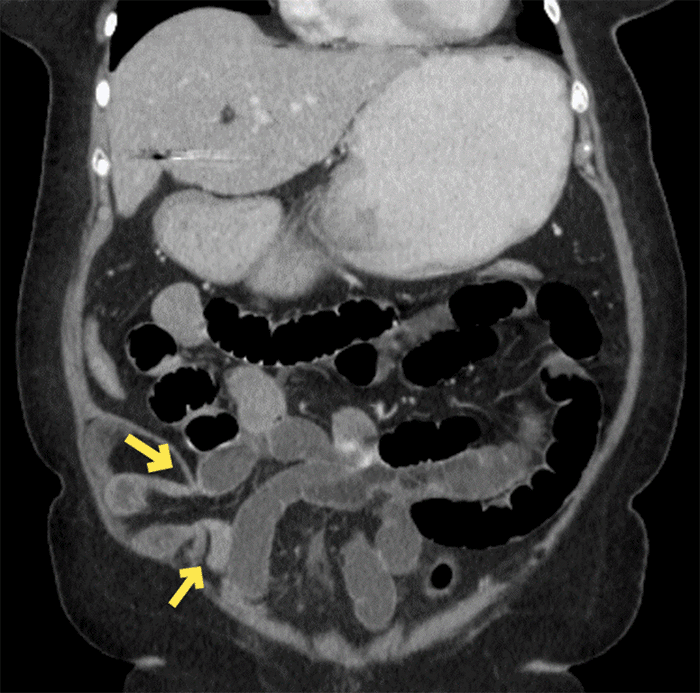

The patient is a 78-year-old female with a history of open appendectomy, open cholecystectomy, and open hysterectomy presented with typical bowel obstruction symptoms, including abdominal pain, distension, nausea, and vomiting. She was hemodynamically stable and with normal labs but exquisitely tender over an indiscrete bulge in her right lower quadrant, which was not reducible. A CT abdomen and pelvis demonstrated bowel obstruction as a result of a Spigelian hernia, as shown in Figure 1 and Figure 2.

Figure 2. Coronal View of Spigelian-type Incisional Hernia with Dilated Proximal Bowel Entering Hernia (cranial) and Decompressed Loop of Bowel Exiting Hernia (caudal). Published with Permission

Note compression of the herniated ileum and free fluid within the hernia sac